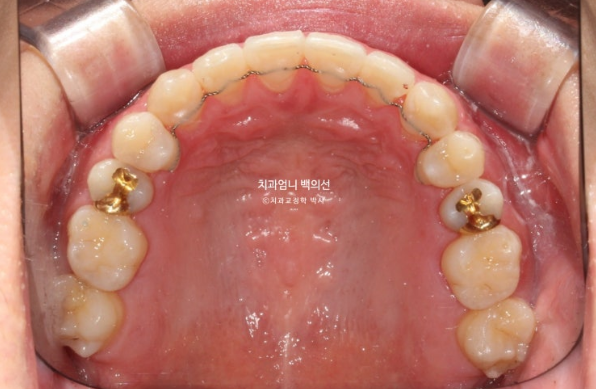

The upper arch widened through the palatal expansion device

23.01~25.03

Even after palatal expansion, the buccal corridor does not necessarily disappear.